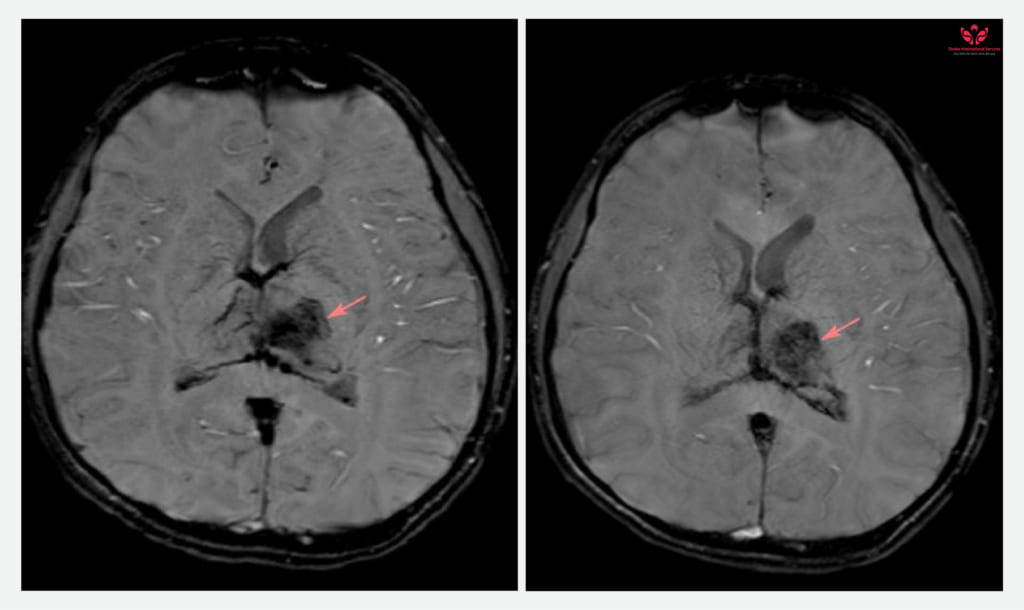

Kết quả ghi nhận tình trạng xuất huyết não, phù não vùng đồi thị. Các bác sĩ của 2 bệnh viện cùng hội chẩn, đưa ra chẩn đoán xác định là đột quỵ xuất huyết não do tắc tĩnh mạch Galen. Sau khi có kết quả hội chẩn, gia đình em được các bác sĩ Bệnh viện Nhi đồng TP. Cần Thơ hướng dẫn nhập viện can thiệp điều trị cấp cứu tại Bệnh viện ĐKQT S.I.S Cần Thơ.

Là bác sĩ can thiệp trực tiếp cho em L.N.T, ThS. BS Lê Minh Thắng – Đơn vị Can thiệp mạch DSA, Bệnh viện ĐKQT S.I.S Cần Thơ cho biết: “Trường hợp của em T. khá hiếm gặp trên thực tế. Dựa trên kết quả chụp MRI của em T. ghi nhận tình trạng xuất huyết não kết hợp với phù vùng đồi thị. Tình trạng bệnh khá nặng cần chỉ định can thiệp sớm để khai thông tĩnh mạch bị tắc nghẽn. Sau khi có kết quả hội chẩn, em được gia đình chuyển ngay sang Bệnh viện ĐKQT S.I.S Cần Thơ. Ngay sau đó, ekip đã tiến hành can thiệp cấp cứu cho em.

Chúng tôi đã tiến hành can thiệp lấy ra rất nhiều cục máu đông trong tĩnh mạch Galen và xoang thẳng và khai thông được tĩnh mạch bị tắc nghẽn. Sau can thiệp, em được hồi sức tích cực, duy trì kháng đông đường uống dự phòng máu đông. Sau thời gian điều trị, tri giác và sức cơ của em đã cải thiện có thể đi lại, hết đau đầu… ”.